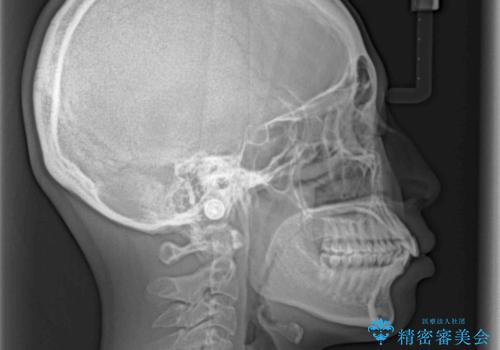

咬合力が非常に強く、咬合力で前歯が前方に押し広げられており、上下唇に閉じにくさが認められました。

上下左右の第一小臼歯4本を抜歯し、ワイヤー装置にて矯正治療を行うこととしました。

強い咬合力により前歯の隙間がなかなか閉じられず、治療期間は長いものとなりましたが、横顔の印象が大きく変わるほど口元の印象を改善することができました。